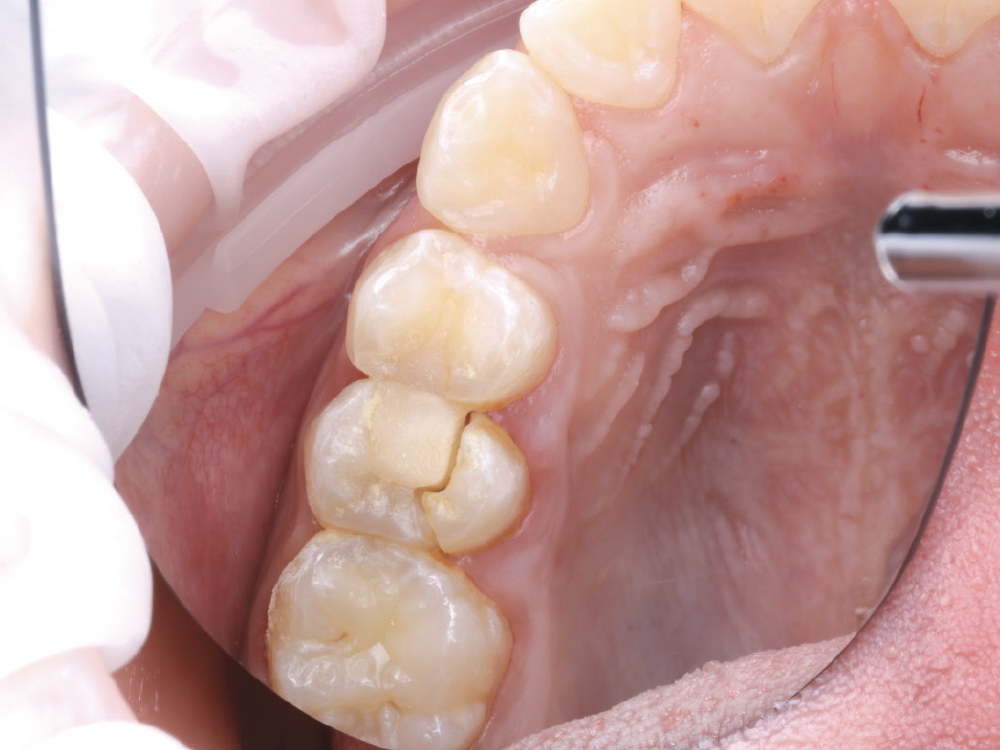

An effective way to build keratinized tissue on the facial is by using a modification of Abrams’ roll technique for localized alveolar ridge augmentation, or the buccal roll.1 This simple technique uses deepithelialized palatal tissue to fold underneath buccal mucosa and create the necessary amount of keratinized tissue for an ideal functional and esthetic outcome.2 This case study will demonstrate how to use this technique by analyzing a mandibular premolar that required an implant restoration.